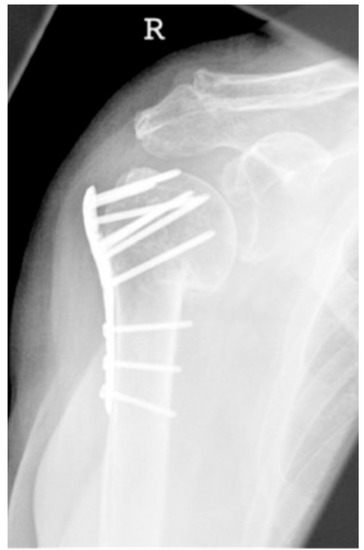

| Complication Type | Exemplary Images by X-rays or Pattern Images | Definition |

|---|---|---|

| 4 | ![]() | Complication Type 4a is based on the presence of AVN of the humeral head without concomitant destruction of the glenoid articular surface due to an associated screw cutout through the humeral head cortex. |